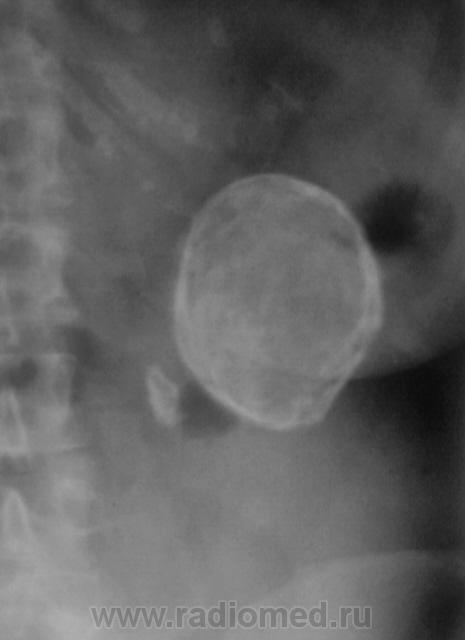

Больше данных за обызествленную кисту неясного генеза.

Обезыствленная полость в почке в сочетании с нефросклерозом. Помимо эхинококка нельзя исключить и обезыствленную туб. каверну. Туберкулез тоже, как известно, любит кальций.

Вполне м.б. закрытой эхинококковой кистой почки (или не почки) в сочетании с камнем. Возможно, у меня богатая фантазия, но, что за тень бобовидной формы слева на уровне Th12 - L1? Из опыта знаю, результаты УЗИ иногда лучше не принимать во внимание.

По снимку данное образование находится в проекции почки , правая-то хорошо визуализируется. А слева?

Интересно, а что, это, рядом с такой "каменюкой", маленькая "каменючка"?

"Младший братик" в синусе почки!

Тогда, выходит допустимо, предположить, что "булыжник" в почке, в лоханке?

Ребра тоже с известью... Склонность к кальцинозу. А не эхинококк? Протокол УЗи вызывает огромное сомнение в квалификации врача...

Один из коллег, ранее, высказал предположение, что имеет место, быть эхинококк селезенки.